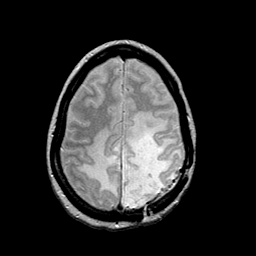

MR Study #2 -- Slice #39